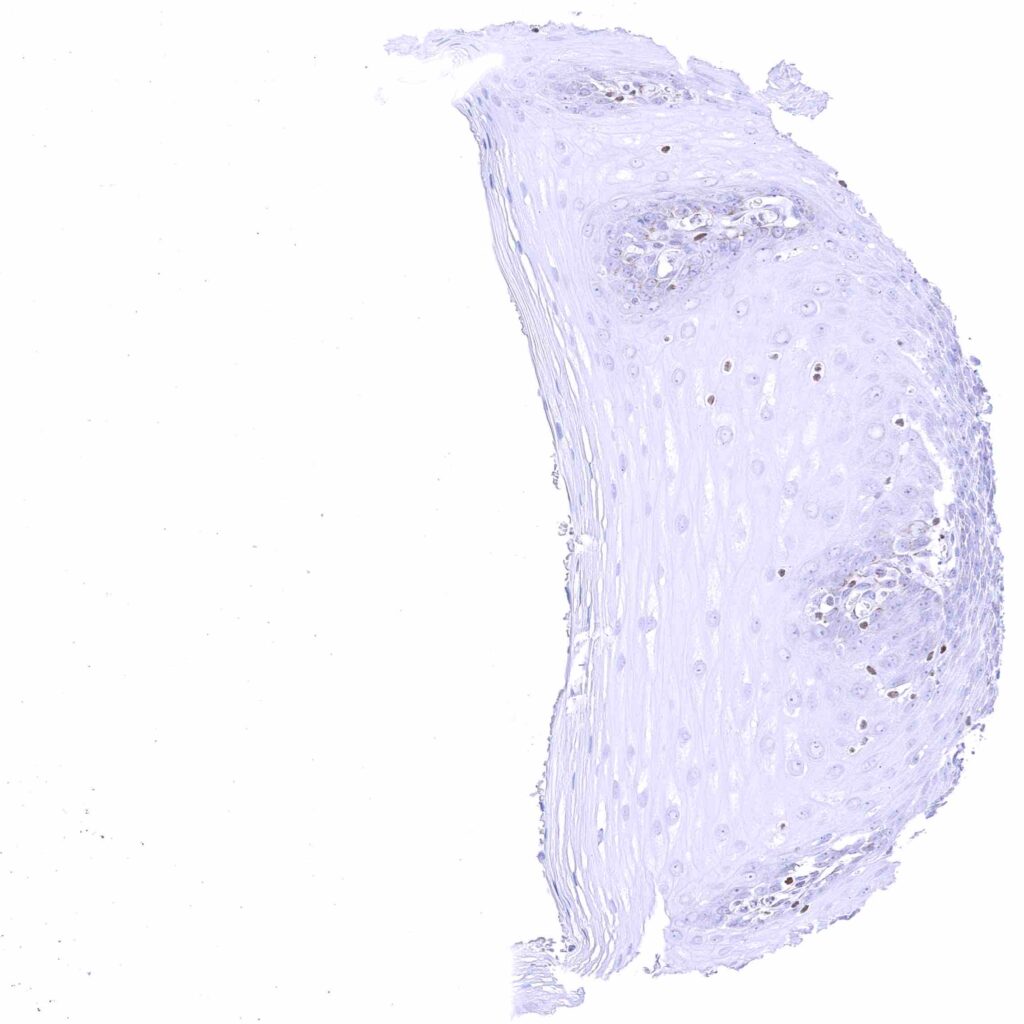

Prostate – Weak to moderate, nuclear GATA3 staining of basal cells. .jpeg